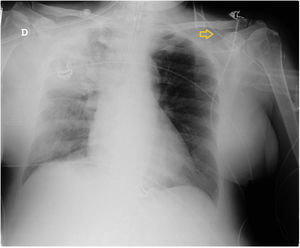

This is the case of a patient admitted to the intensive care unit with signs of right sided pneumonia. A peripherally inserted central catheter (PICC) is cannulated for intravenous treatment. The thoracic x-ray performed reveals that the catheter does not land in the right atrium following a trajectory at clavicle level (Fig. 1). Six days after admission the PICC is removed revealing the presence of neck cellulitis at left jugular vein. The vascular ultrasound performed confirms the presence of venous thrombosis from the cannulation area of the PICC in the mid left cephalic vein (LCV) progressing through the cephalic vein (CV) until it reaches the external jugular vein (EJV) through a segment of supraclavicular anomalous venous communication (AVC) (Figs. 2 and 3).